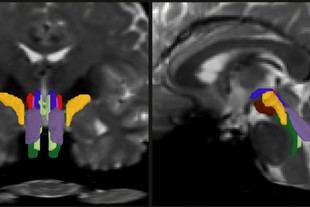

Salud Tecnología

ASUS Healthcare presenta innovaciones en imagen médica y AI en MEDICA 2025

14/11/2025@10:52:00